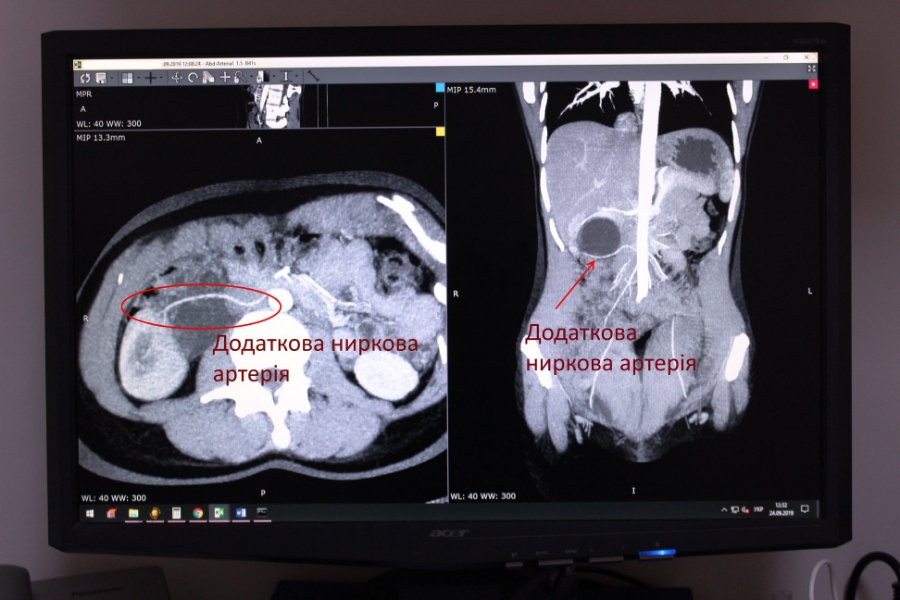

У медзакладі зазначають, що пацієнтка була направлена на комп'ютерну томографію з єдиною скаргою – ниючий біль в попереку справа, який турбував останні пів року. В результаті дослідження у жінки виявили синдром Фролея (вроджена аномалія розвитку ниркових артерій) та гідронефроз.